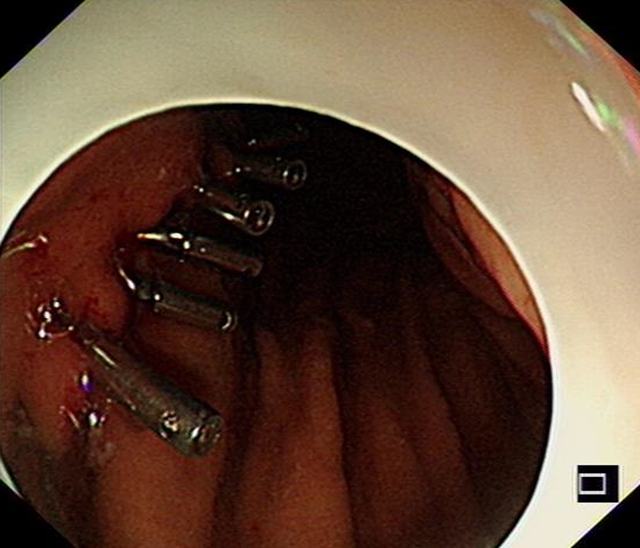

“科室团队进行了充分讨论,在取得家属的同意后,决定分两步走,先由科室的介入团队(朱清亮主治医师与张海龙博士)进行胃黏膜下肿物介入栓塞治疗,‘堵塞’患者胃左动脉分支血管,将肿瘤‘饿死’。隔一段时间后,再由汤小伟副教授进行内镜下ESD切除术剥离肿瘤。”汤小伟副教授说,这是消化内科的一次有益尝试,在国内也并不多见。

1月后复查CT与胃镜,患者瘤体有明显缩小,并且供血的主要动脉血管已经完全被栓塞。

CT检查提示体内的胃黏膜下肿瘤有所缩小,意味着栓塞成功。而后,汤小伟副教授为李婆婆进行内镜下ESD切除术。他带领团队在患者胃黏膜表面开一个小口,内镜经由这个小口在黏膜下层建“隧道”直至肿瘤位置,再将肿瘤和周边组织分离后切除取出。50分钟左右,手术顺利完成。最终的病理结果提示肿物的性质为胃间质瘤(低危险度),属于预后较好的一种类型。